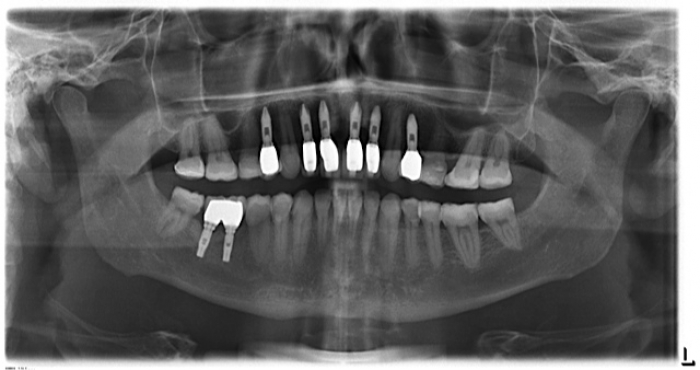

Imagem após substituição das próteses de porcelana

Raio x após substituição das próteses de porcelana